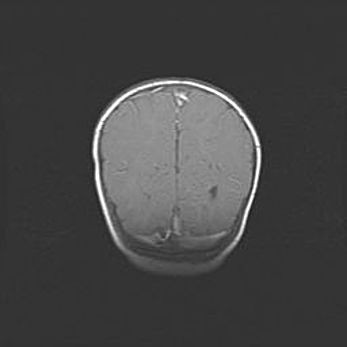

Открытая гидроцефалия.

Возраст: 6 месяцев 15 дней

Вес: 6200 г

Пол: женский

Окружность головы: 41 см

Срок гестации: 38 недель

Гидроцефалия головного мозга у новорожденных – это скопление избыточного количества цереброспинальной жидкости в головном мозге. Ее избыточное скопление в мозге приводит к патологическому расширению желудочков мозга (четырех полостей, расположенных в глубине белого вещества мозга, заполненных цереброспинальной жидкостью и связанных узкими проходами).

Открытый тип гидроцефалии (сообщающаяся) наблюдается тогда, когда нарушен механизм всасывания ликвора в системный кровоток. При этом типе причиной заболевания чаще всего является перенесенные ранее инфекции (например: менингит),  либо же наличие крови в субарахноидальном пространстве.